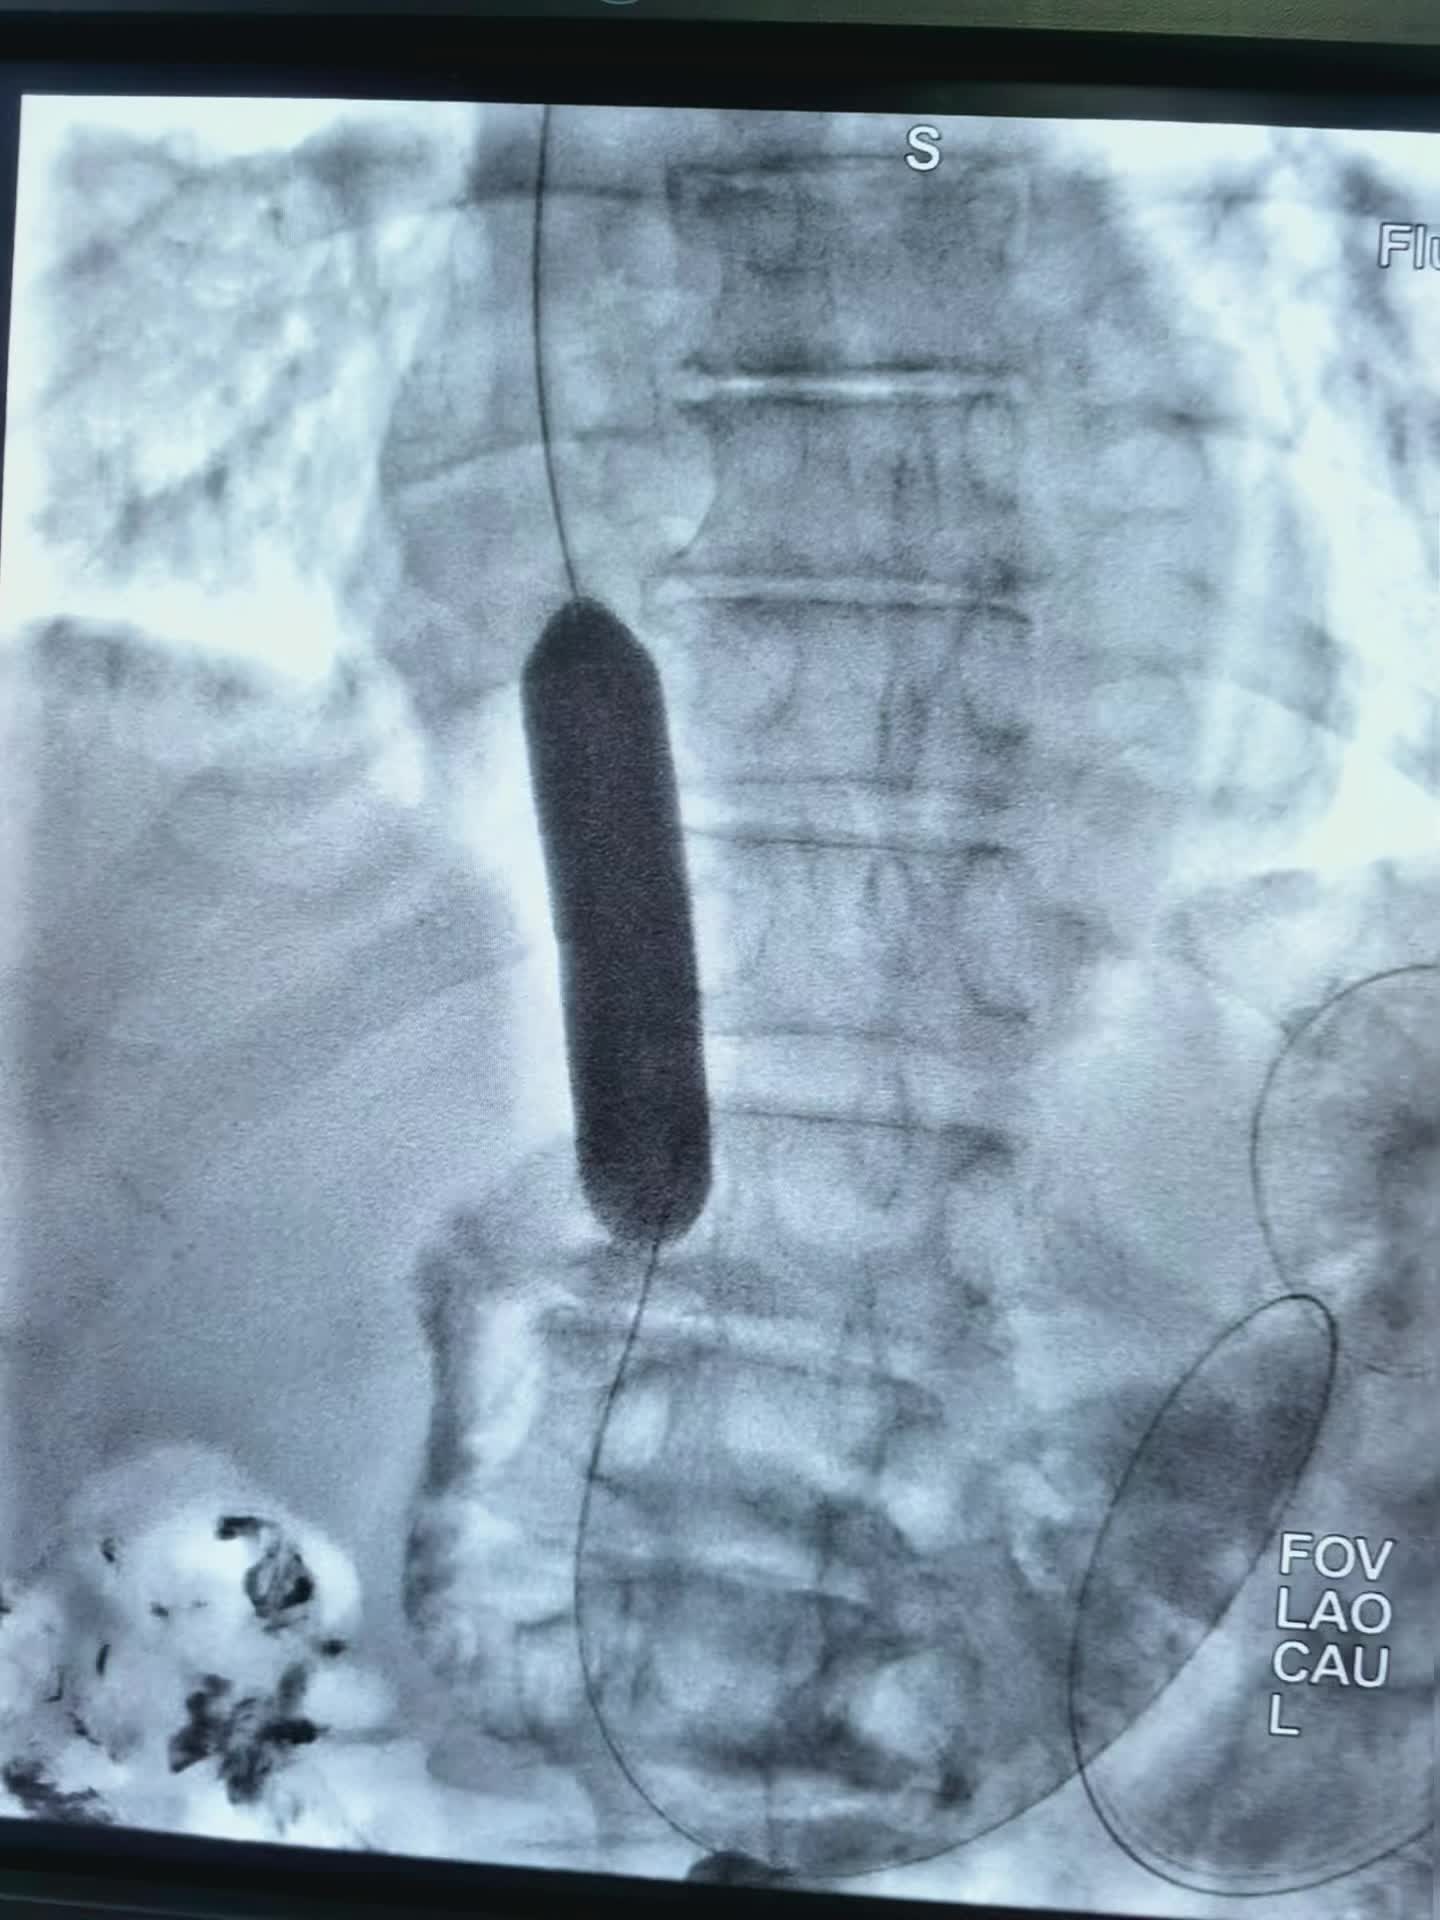

上午第一台78岁老年男性贲门癌患者,突发食管梗阻不能进食水,行球囊扩张,食管支架置入术,术即可恢复饮食。 第二台:食管癌术后3年再次进食哽咽,食管吻合口狭窄伴肠管膈肌处狭窄。单纯行球囊扩张术,术后即可恢复正常饮食。